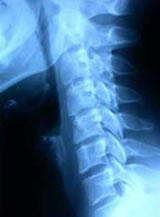

• Radiografía de la columna vertebral para descartar otras causas de dolor cervical o de espalda. Sin embargo, no es posible diagnosticar una hernia de disco únicamente por medio de una radiografía de la columna; aunque es de gran utilidad para evaluar la curvatura espinal, la presencia de artrosis y otras alteraciones óseas.